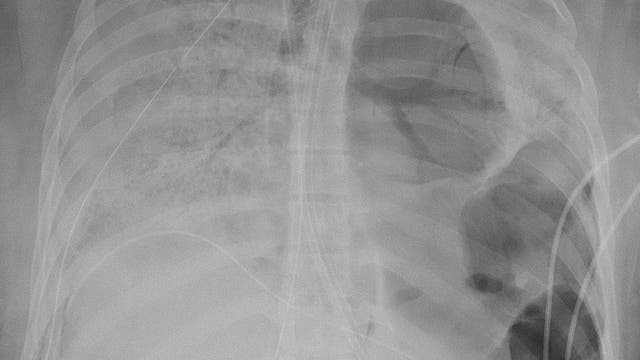

Woman in her 20s receives double lung transplant after suffering ‘irreversible damage’ from COVID-19

The procedure was the first of its kind in the U.S. since the pandemic began. Doctors said she was otherwise healthy.